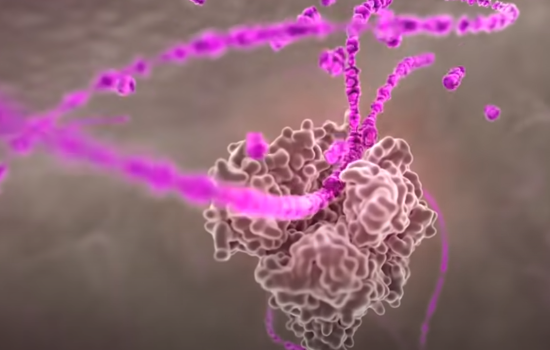

其中,在冠状突起中最重要的一种蛋白叫做刺突糖蛋白(蓝色),这种蛋白可以识别人体细胞的表面ACE2蛋白(黄色)。举个例子,ACE2蛋白像一把锁,一般只有配对的钥匙才能打开它进入细胞内部。一颗合格的病毒会利用自己的技能合成出一把刺突糖蛋白仿制钥匙,堂而皇之的侵入细胞。这个过程就像这样:

如果识别成功,那么接下来在蛋白质外壳的协助下,病毒会使用细胞融合技能进入人体细胞。

整个过程就像病毒利用自己仿制的钥匙开启了人体细胞的大门。